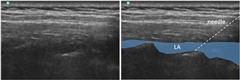

平行法で針をすすめ、0.375%ロピバカイン30mLを注入したのが次の図です。

傍脊椎ブロック,retrolaminar block,paravertebral block,椎弓板

針の向こうは骨ですから、気胸などの合併症を気にすることはありません。

背部正中線から1.5cmですから、ブラインドでも比較的安全に施行できます。